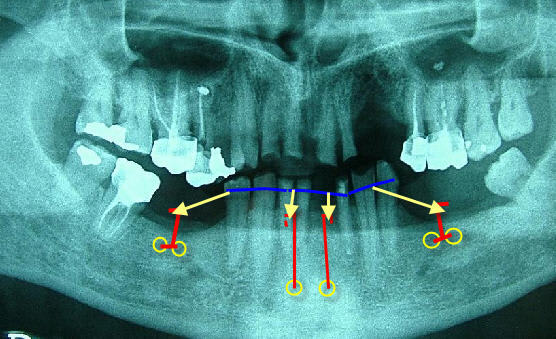

Comme on manque d’ancrage dentaire pour ingresser, il faut prendre des appuis directs osseux, et mettre des vis dans la symphyse mandibulaire. Je réalise cela depuis plusieurs années, c’est très efficace, facile à faire et très bien toléré par les adultes. Suites opératoires simples avec uniquement du paracétamol pendant 2 jours.

Deux vis de chirurgie maxillo-faciales en parasymphysaire avec des ligatures émergentes sur lesquelles sont accrochées des chaînettes élastomériques attachées aux couronnes des dents à ingresser.

Comme l’appui est vestibulaire, cela entraîne un mouvement parasite des dents vers l’avant qu’il faut neutraliser, voire inverser. D’où traction distale supplémentaire grâce à deux fois deux vis en tandem avec une potence verticale dans les zones édentées latérales.

Photos jointes : un schéma à partir de la pano et des exemples clinique (pas exactement ton cas, mais pour te donner une idée du système).